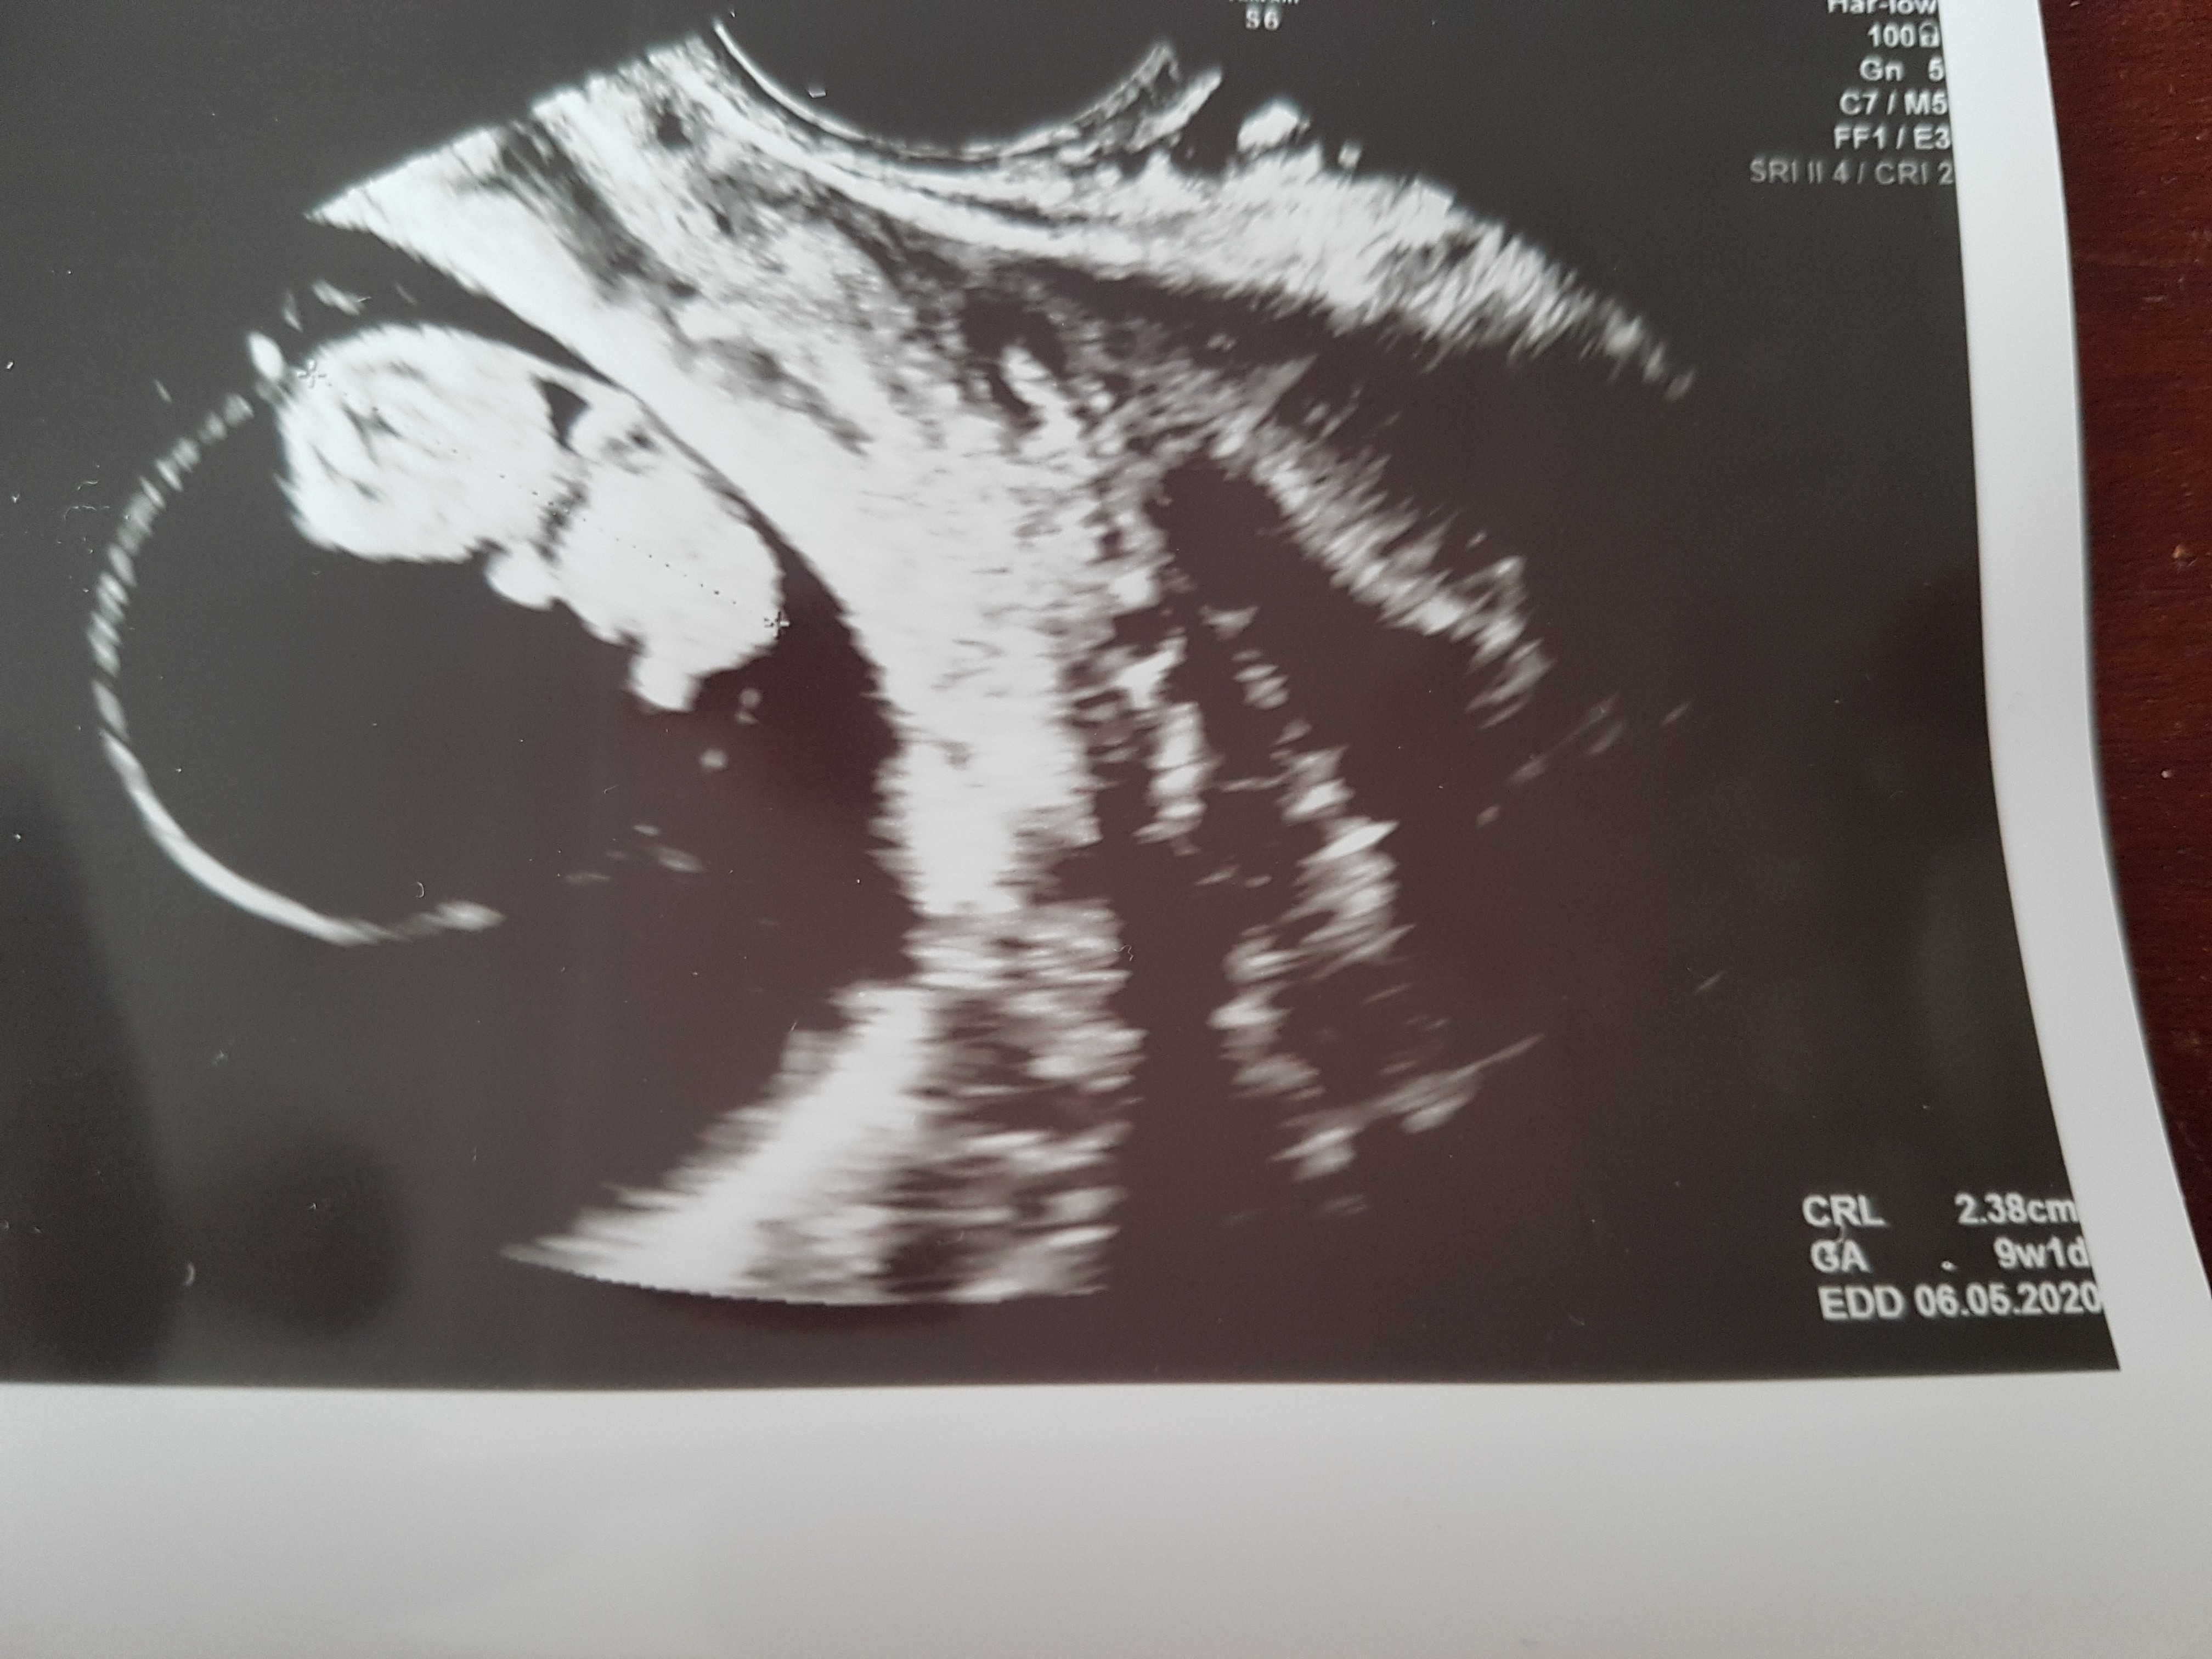

To ja też tutaj dołączę zdjęcia z ostatnich wizyt. Te zdjęcia sprawiły mi największą radość podczas tej ciąży.

Zobacz załącznik 1031910

Już ludzik, a nie krewetkaOstatnie zdjęcie rozwalił mnie na Łopatki[emoji173]️[emoji173]️[emoji173]️[emoji173]️[emoji173]️